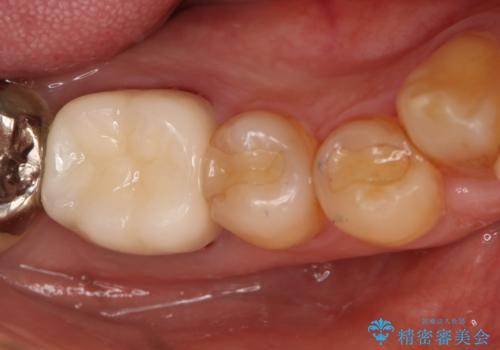

- 保険で治療された右下5番をセラミックにやり変え希望の患者様です。

切削量などを考慮し、セラミックインレーでの治療を選択しました。

古い材料と虫歯を全て除去した上で形成・印象を行い、セラミックインレーを装着しています。